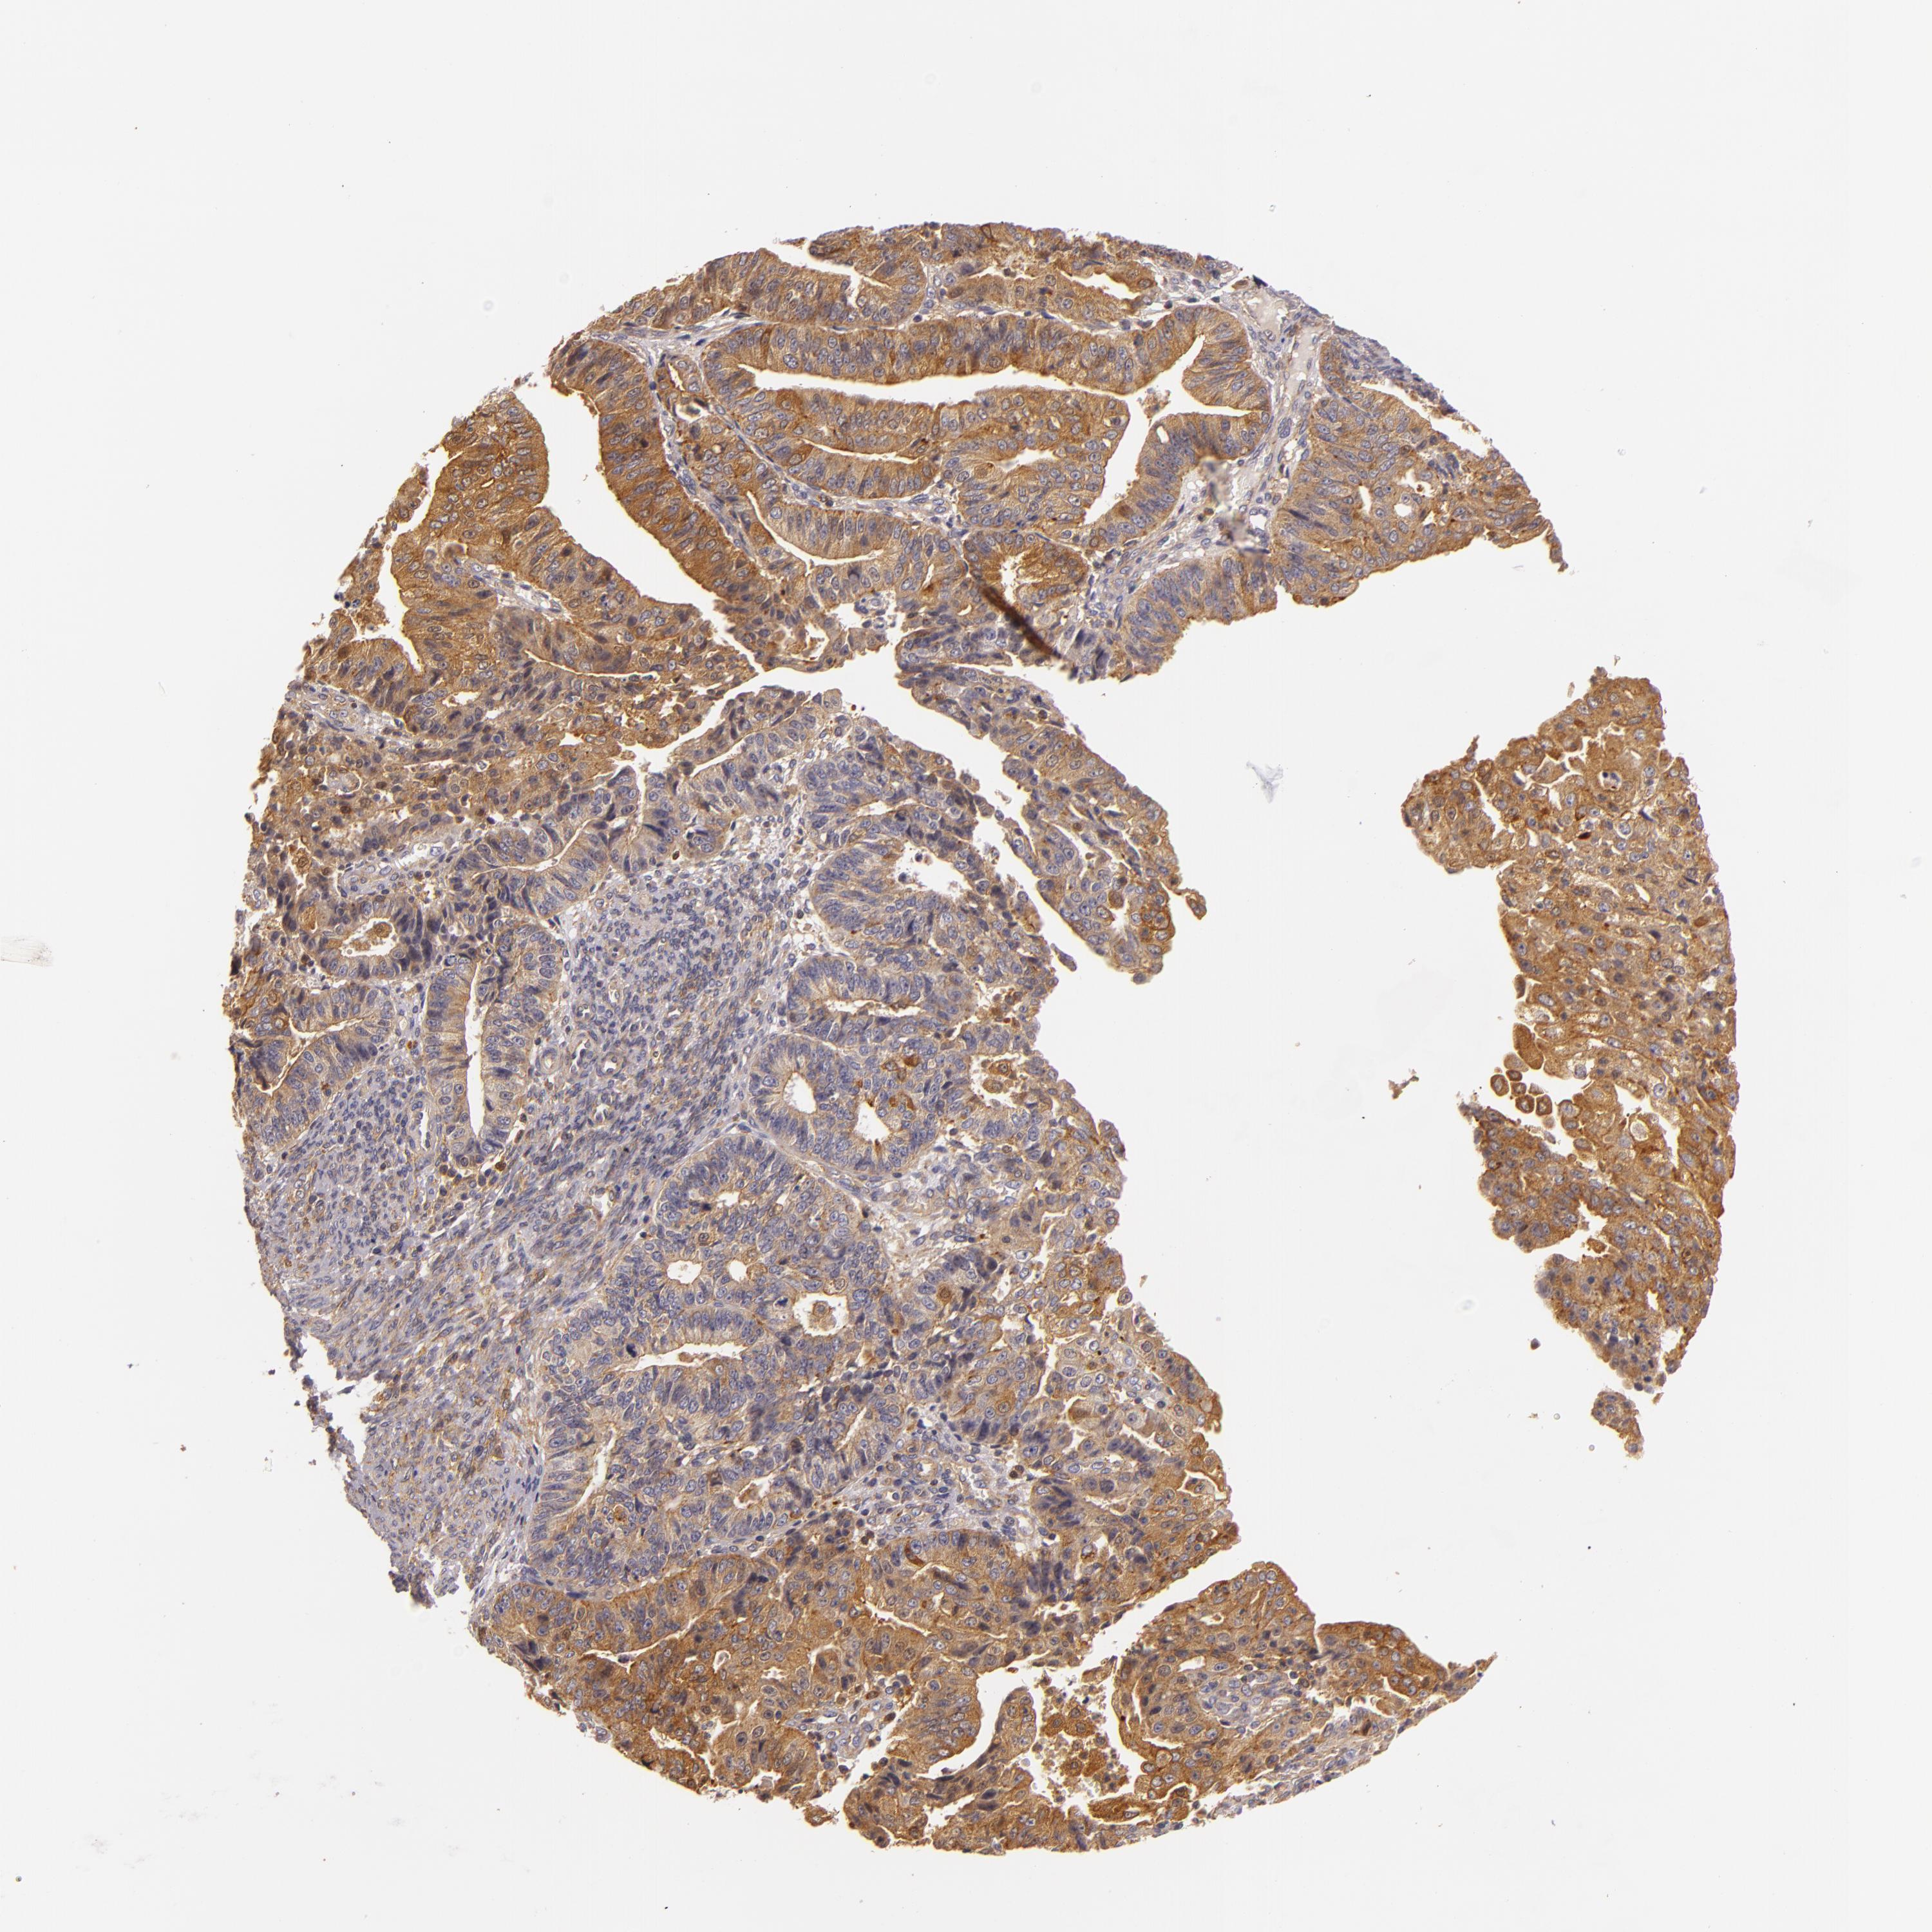

ENDOMETRIAL CANCER - Protein expressioni

A mouse-over function shows sample information and annotation data. Click on an image to view it in a full screen mode. Samples can be filtered based on level of antibody staining by selecting one or several of the following categories: high, medium, low and not detected. The assay and annotation is described here.

Note that samples used for immunohistochemistry by the Human Protein Atlas do not correspond to samples in the TCGA dataset.

Antibody stainingi

Antibody staining in the annotated cell types in the current human tissue is reported as not detected, low, medium, or high, based on conventional immunohistochemistry profiling in selected tissues. This score is based on the combination of the staining intensity and fraction of stained cells.

Each image is clickable and will lead to virtual microscopy that enables deeper exploration of all samples and also displays staining intensity scores, fraction scores and subcellular localization as well as patient and tissue information for each sample.

Antibody HPA001749

Staining

High

Medium

Low

Not detected

Intensity

Strong

Moderate

Weak

Negative

Quantity

>75%

75%-25%

<25%

None

Location

Nuclear

Cytoplasmic/membranous

Cytoplasmic/membranous,nuclear

Adenocarcinoma, NOS